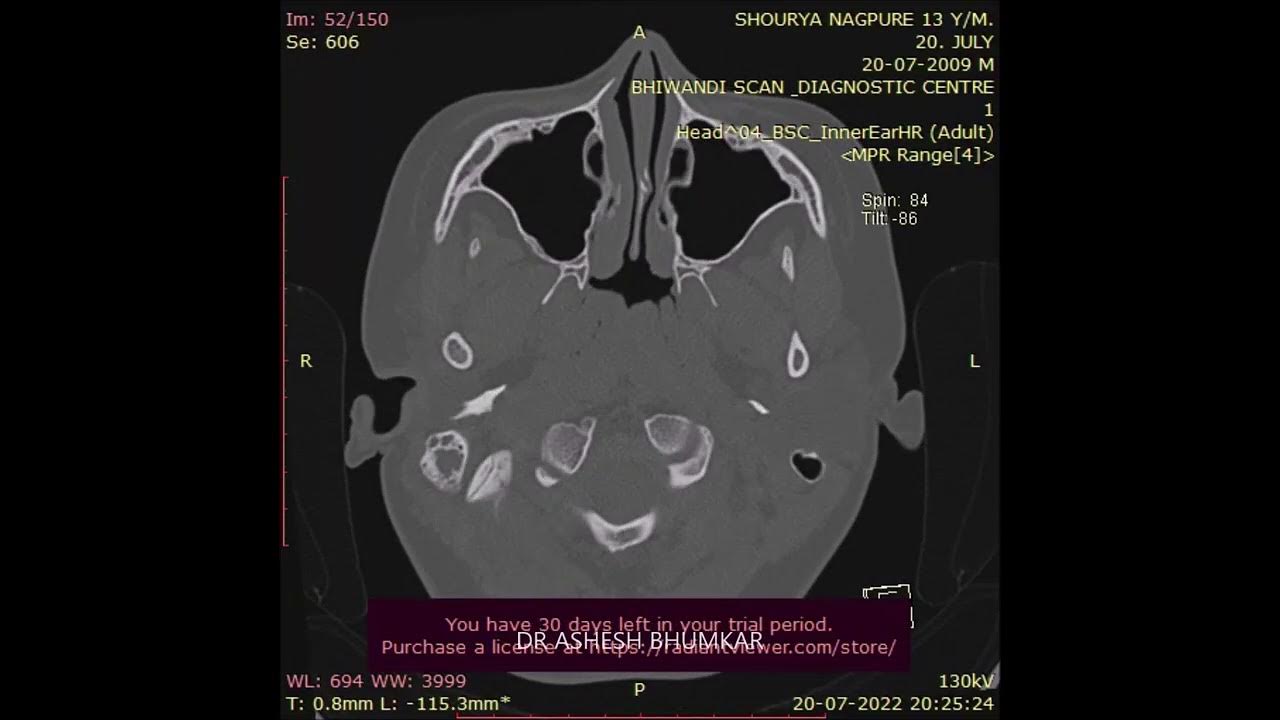

FACIAL NERVE BIFID... Lt. Ear Exploration For Hearing Surgery by Dr Facial Nerve Exploration data were extracted, examined and analyzed to attain information such as, patient demographics, extracranial branch. It contains the motor, sensory, and parasympathetic (secretomotor) nerve. Electroneuronography (enog) involves electrical stimulation of the facial nerve at or near the stylomastoid foramen. facial nerve emg monitoring during acoustic neuroma surgery can protect the nerve effectively from damage. The facial nerve (cranial. Facial Nerve Exploration.